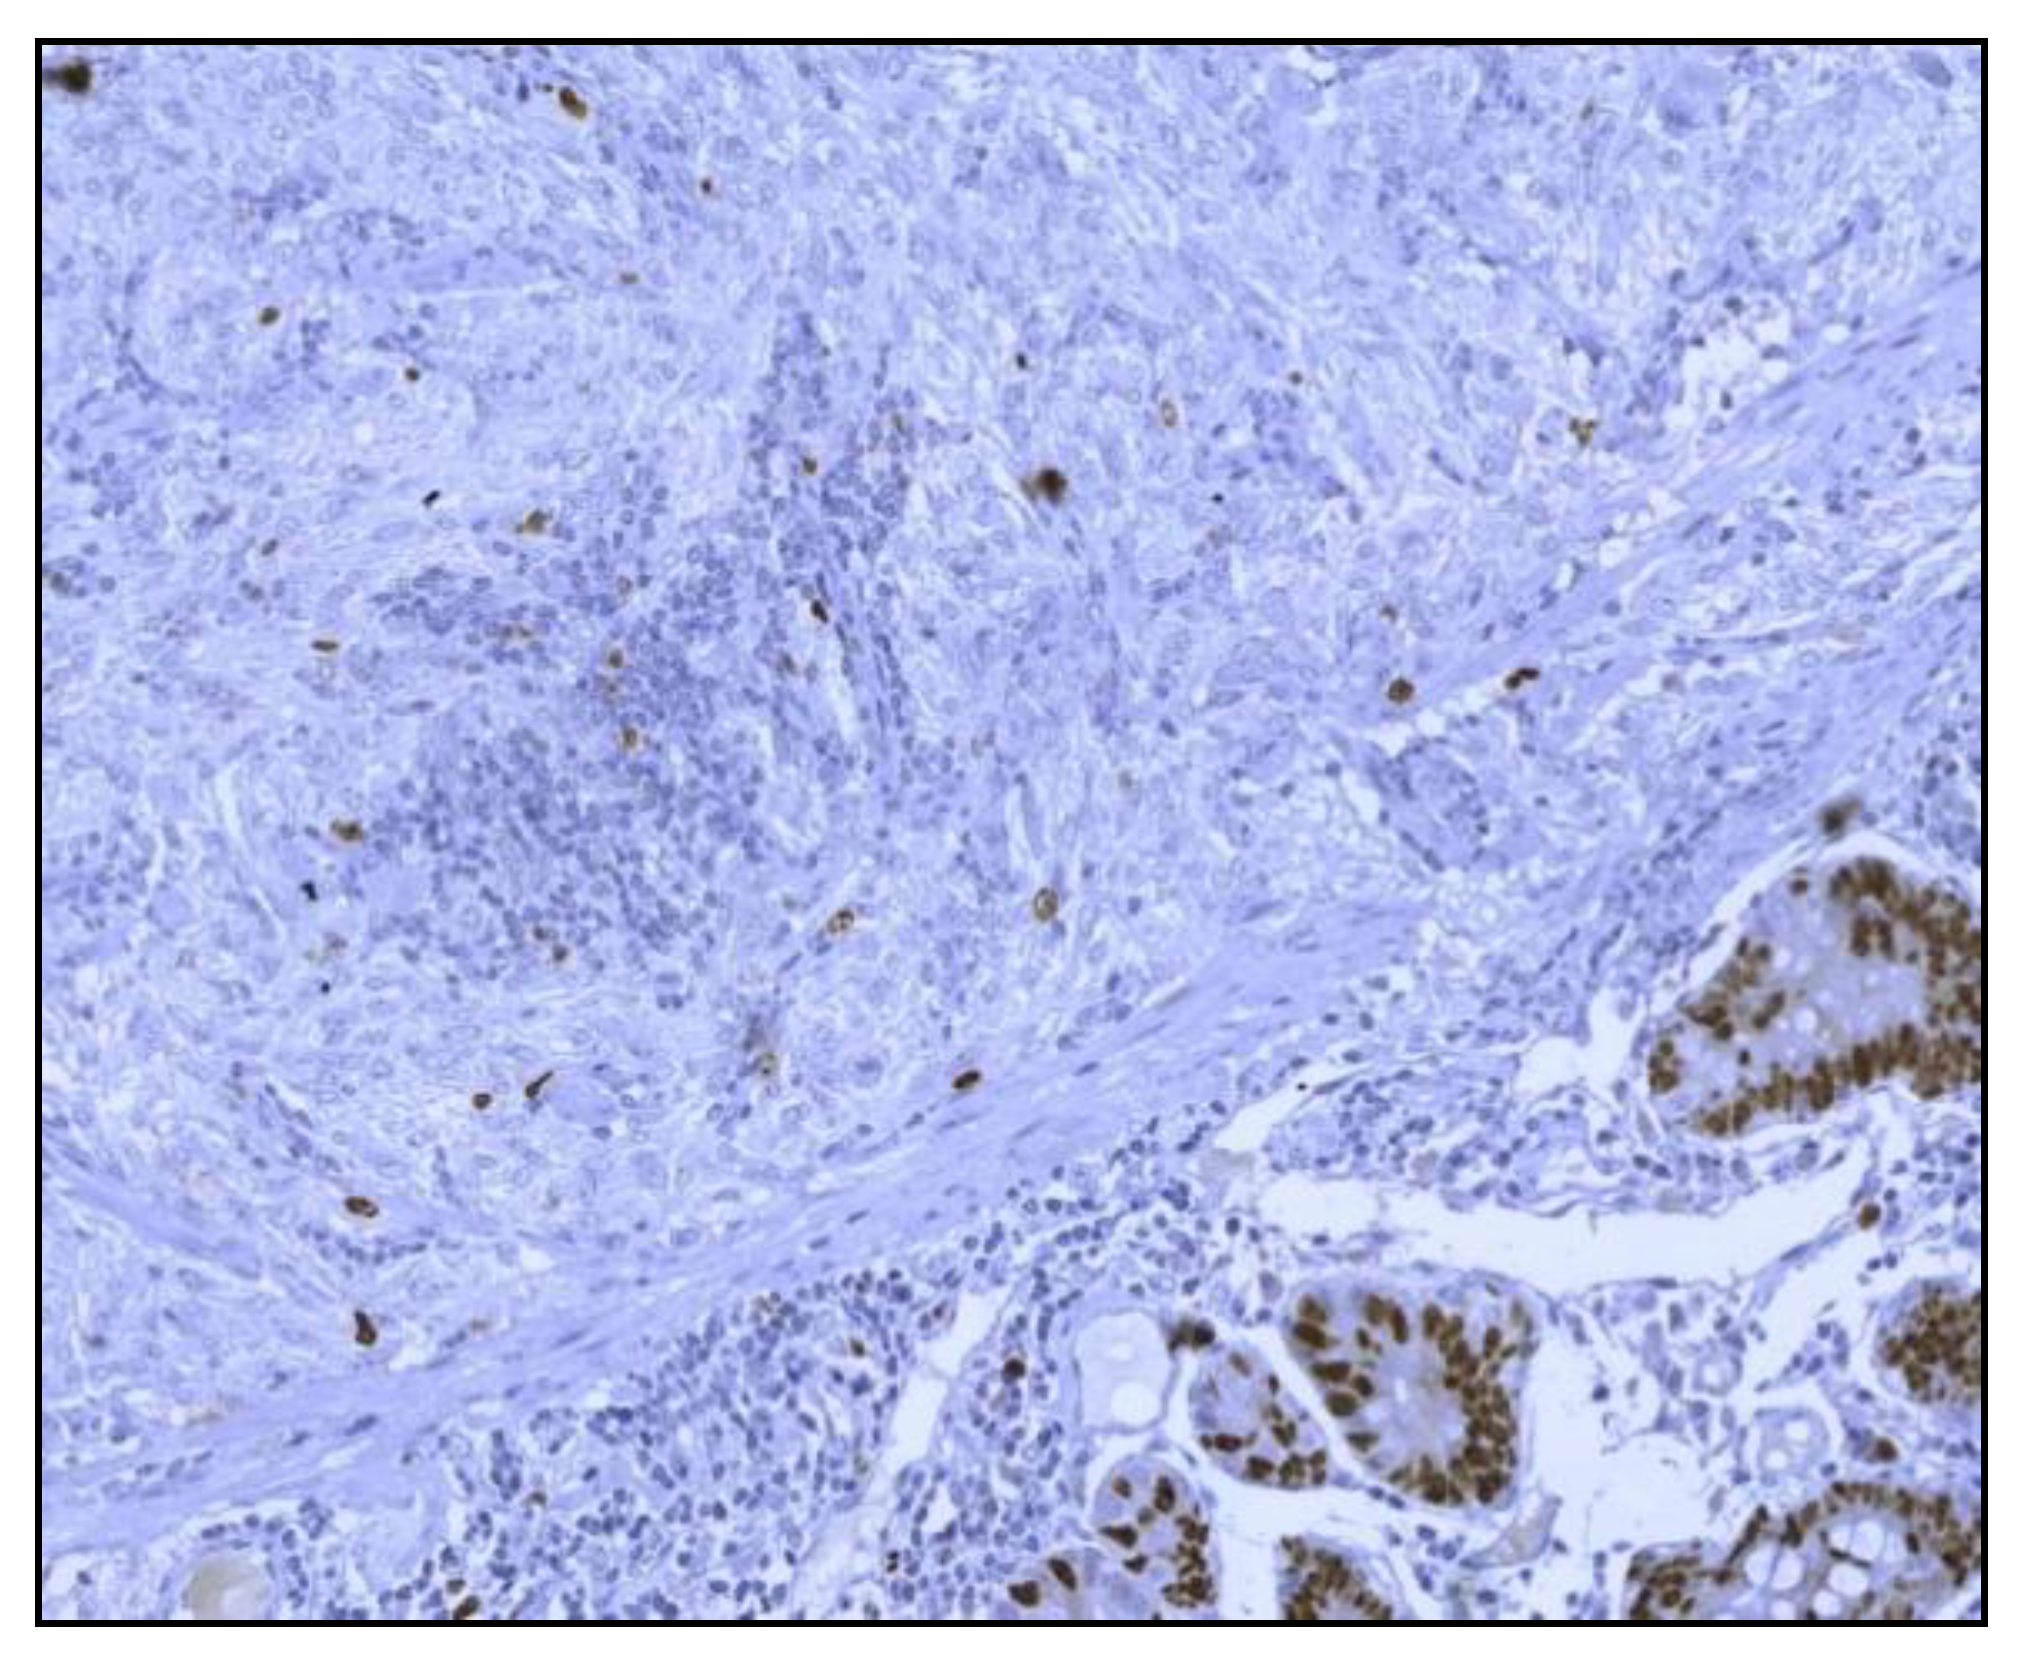

After nasogastric tube positioning, the upper endoscopy revealed dilated hypotonic stomach and duodenum with lesions of erosive gastritis and duodenitis. Using barium study of the upper gastrointestinal tract, we found a filling defect of the fourth portion of the duodenum, with dilated stomach and duodenum proximal to the site of obstruction; we also found gastroesophageal reflux without radiological signs of hiatal hernia (Figure 1). Ultrasonography and CT scan showed no metastases.

Figure 1. Barium study of the upper gastrointestinal tract filling defect of the fourth portion of the duodenum with dilated stomach and duodenum proximal to the site of obstruction and gastroesophageal reflux without radiological signs of hiatal hernia.